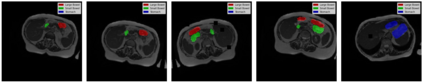

Gastro-Intestinal Tract cancer is considered a fatal malignant condition of the organs in the GI tract. Due to its fatality, there is an urgent need for medical image segmentation techniques to segment organs to reduce the treatment time and enhance the treatment. Traditional segmentation techniques rely upon handcrafted features and are computationally expensive and inefficient. Vision Transformers have gained immense popularity in many image classification and segmentation tasks. To address this problem from a transformers' perspective, we introduced a hybrid CNN-transformer architecture to segment the different organs from an image. The proposed solution is robust, scalable, and computationally efficient, with a Dice and Jaccard coefficient of 0.79 and 0.72, respectively. The proposed solution also depicts the essence of deep learning-based automation to improve the effectiveness of the treatment

翻译:胃内肠道癌被认为是GI大片器官致命恶性病,由于其致命性,迫切需要医疗图象分解技术,以便分器官减少治疗时间,加强治疗;传统分解技术依靠手工制作的特征,计算成本低,效率低;许多图像分类和分解任务中,视觉变形器受到极大欢迎。从变压器的角度来看,为了解决这一问题,我们引入了混合型CNN-传输结构,将不同器官与图像分割开来。 拟议的解决办法是稳健、可缩放和计算效率高的,Dice和Jacccard系数分别为0.79和0.72。 拟议的解决办法还描述了深层学习自动化的本质,以提高治疗的效果。